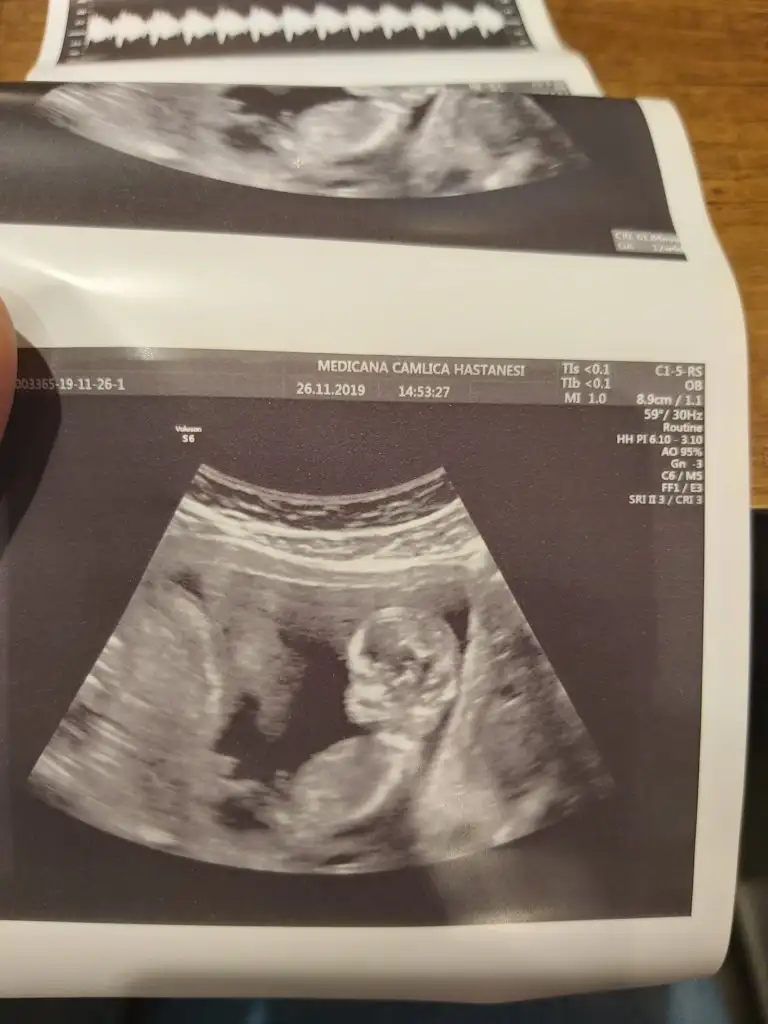

Bana da de banada attım resminiaaa nuba göre erkek canm kaç haftalıktı bu usg

Erkek mi ki acabaTeyzeler bu da bizim fotomuz ☺